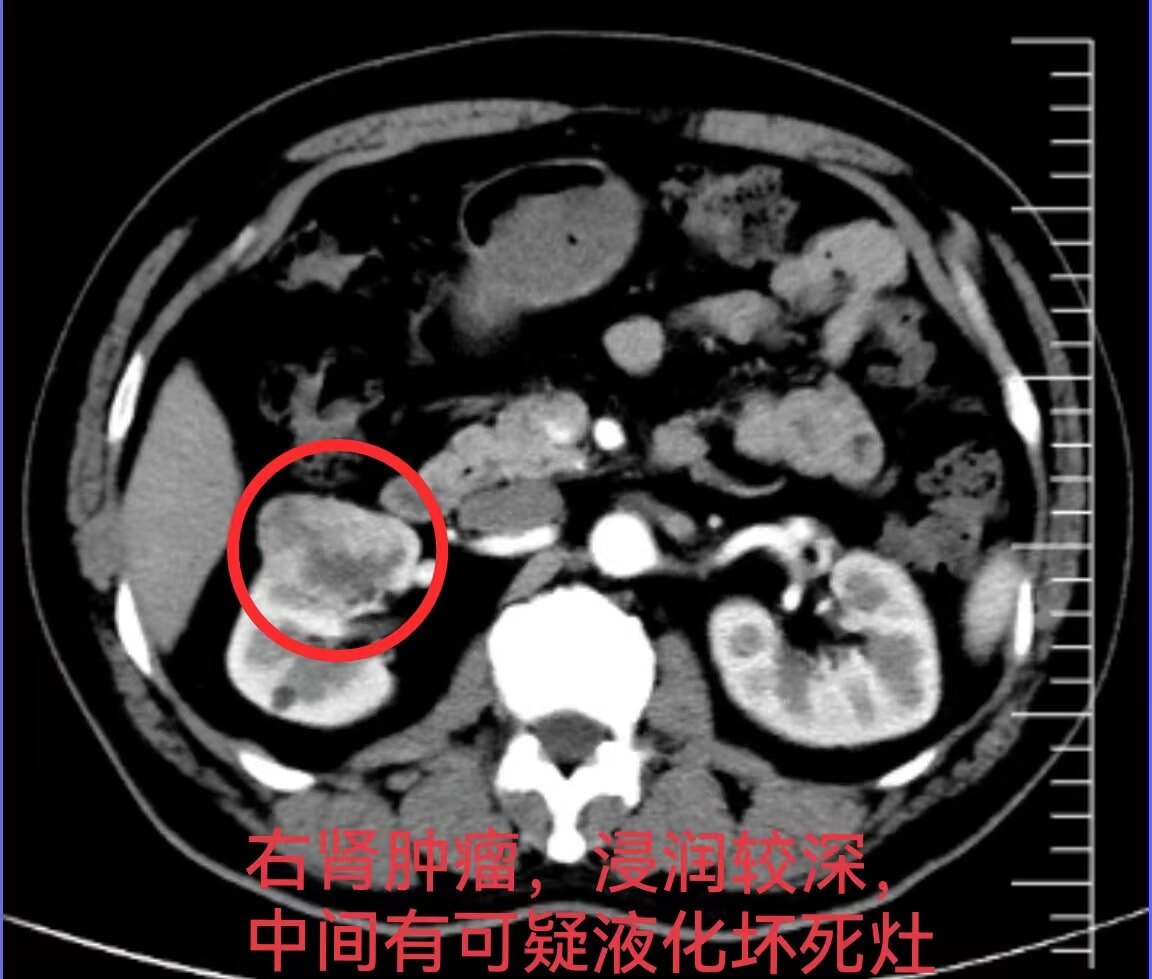

這個(gè)小腎癌,為什么不適合做保腎手術(shù)??今天上午,幫一位59歲的中學(xué)老師做了經(jīng)后腹腔鏡右腎癌根治切除術(shù),術(shù)前CT顯示右腎腫瘤大小約4.3x2.7cm,為什么這個(gè)不是特別大的“小腎癌”不適合做保腎手術(shù)(腎部分切)呢??首先,什么是“小腎癌”呢?臨床上一般把直徑4cm左右,尤其是小于4cm的腎癌稱作“小腎癌”,小于4cm的臨床分期是T1a期,4-7cm是T1b期,是相對(duì)早期的腎癌。一般對(duì)于T1期,尤其是T1a期的腎癌首選做保腎手術(shù)(即腎部分切除術(shù)),?但是,對(duì)于這位患者,從CT影像上看,腫瘤浸潤(rùn)腎臟較深,瘤體大部分位于腎內(nèi),距離腎臟大血管較近;其次,腫瘤形狀不規(guī)則,略呈多中心生長(zhǎng),與周?chē)DI組織邊界不清,包膜不明顯;最后,腫瘤中心有可疑液化壞死灶,表明腫瘤中心癌細(xì)胞生長(zhǎng)速度過(guò)快,營(yíng)養(yǎng)供應(yīng)不及導(dǎo)致細(xì)胞壞死,說(shuō)明細(xì)胞惡性程度可能偏高。?這種小腎癌如果勉強(qiáng)做保腎手術(shù)(腎部分切除術(shù)),極容易造成腫瘤切緣陽(yáng)性,術(shù)中腫瘤破裂等,造成災(zāi)難性后果。?完整切除腎臟(根治性腎切除)后,剖開(kāi)腎臟和腫瘤,驗(yàn)證了手術(shù)前的判斷!腫瘤幾乎沒(méi)有包膜,呈多葉狀多中心生長(zhǎng),腫瘤中心有液化壞死的癌細(xì)胞,腫瘤邊界不清,靠近邊界處還有數(shù)個(gè)5mm的衛(wèi)星病灶!?所以,對(duì)于這樣的“小腎癌”,最佳治療方式是根治性腎切除,而不能勉強(qiáng)做“保腎”手術(shù)。